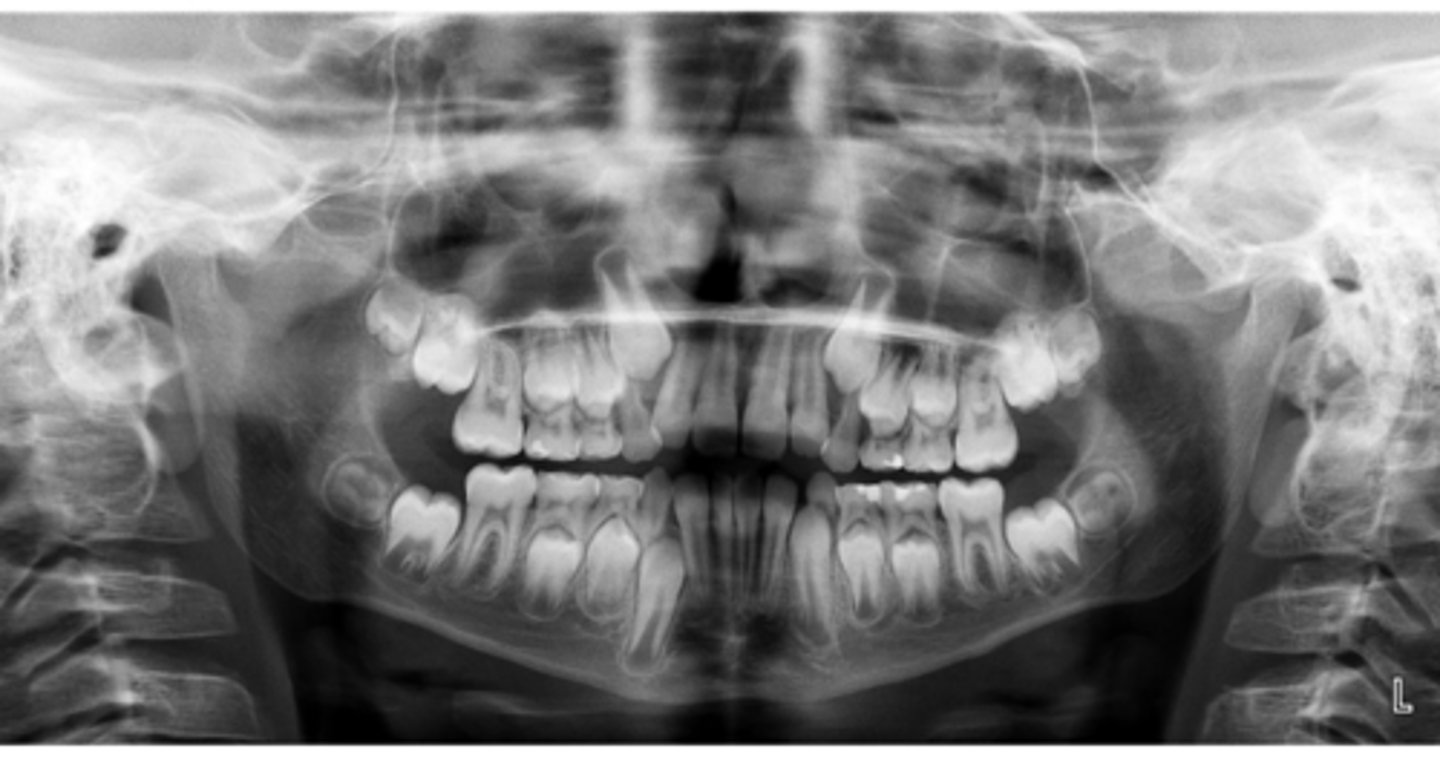

No

Are there congenitally missing teeth in the maxillary arch?

Are there congentially missing teeth in the mandibular arch?

Any supernumerary teeth?

Yes - mandibular second molars

Any impacted teeth?

Yes

Are the condyles symmetrical?

Maybe in the upper molars

Are there any dilacerated roots?

Are there congenitally missing teeth in the mandibular arch?

Are there any supernumerary teeth?

Are there retained primary teeth?

A little bit

Is there crowding?

Is there any pathology?

Possibly #20